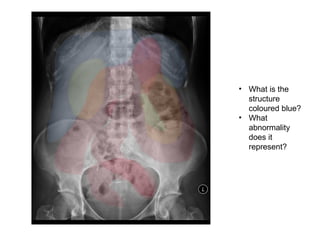

• What is the

structure

coloured blue?

• What

abnormality

does it

represent?

• What isthe structure coloured blue? • What abnormality does it represent?